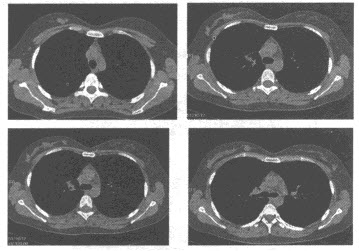

女,26岁,胸部CT扫描见右侧乳腺多发结节状软组织密度影,图像如下,最可能的诊断为()

A . 乳腺腺病

B . 乳腺纤维腺瘤

C . 乳腺癌

D . 乳腺囊肿

E . 乳腺导管内乳头状瘤

女,26岁,胸部CT扫描见右侧乳腺多发结节状软组织密度影,图像如下,最可能的诊断为<img border="0" style="width: 356px; heig

[单选题]女,26岁,胸部CT扫描见右侧乳腺多发结节状软组织密度影,图像如下,最可能的诊断为A.乳腺腺病B.乳腺纤维腺瘤C.乳腺癌D.乳腺囊肿E.乳腺导管内乳头